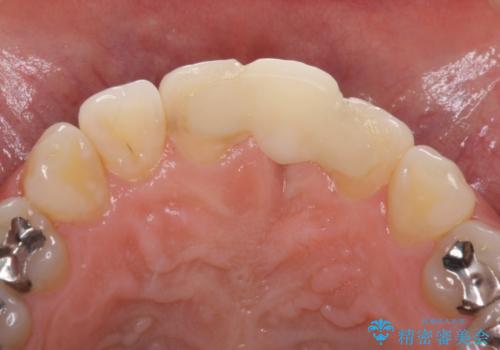

- 接着タイプの前歯のブリッジが不自然であるとのことで来院された患者様です。

欠損部の歯肉が窪んでいるため、歯肉移植により形態を改善し、オールセラミックブリッジにて補綴することとしました。

事前に装着されていた接着タイプのブリッジは、歯の切削量が少ない反面、接着界面から虫歯が進行しやすく、脱落リスクが高くなるというデメリットがあります。